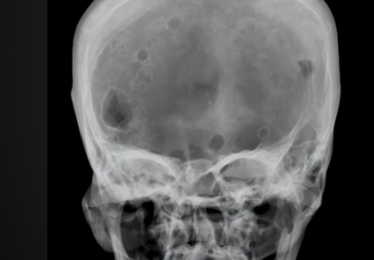

Raindrop skull on X-ray

Metastasis in skull on X-ray